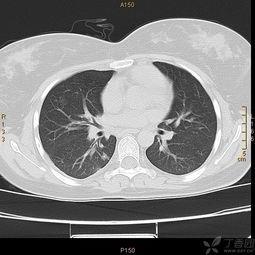

首先,让我们来看看正常鼻骨CT图片的基本结构。这张图片上,你的鼻骨清晰可见,就像是一幅精细的地图。鼻骨位于鼻子的中央,是面部骨骼的一部分。它由两个长条形的骨头组成,形状像字母“V”。

在正常鼻骨CT图片上,你可以看到以下特点:

1. 鼻骨的形状:鼻骨呈长条形,两端较细,中间较粗。

2. 鼻骨的厚度:正常鼻骨的厚度大约在1.5到2.5毫米之间。

3. 鼻骨的密度:与周围骨骼相比,鼻骨的密度略低,但仍然较为致密。

4. 鼻骨的对称性:正常情况下,左右两侧的鼻骨大小、形状和密度基本一致。